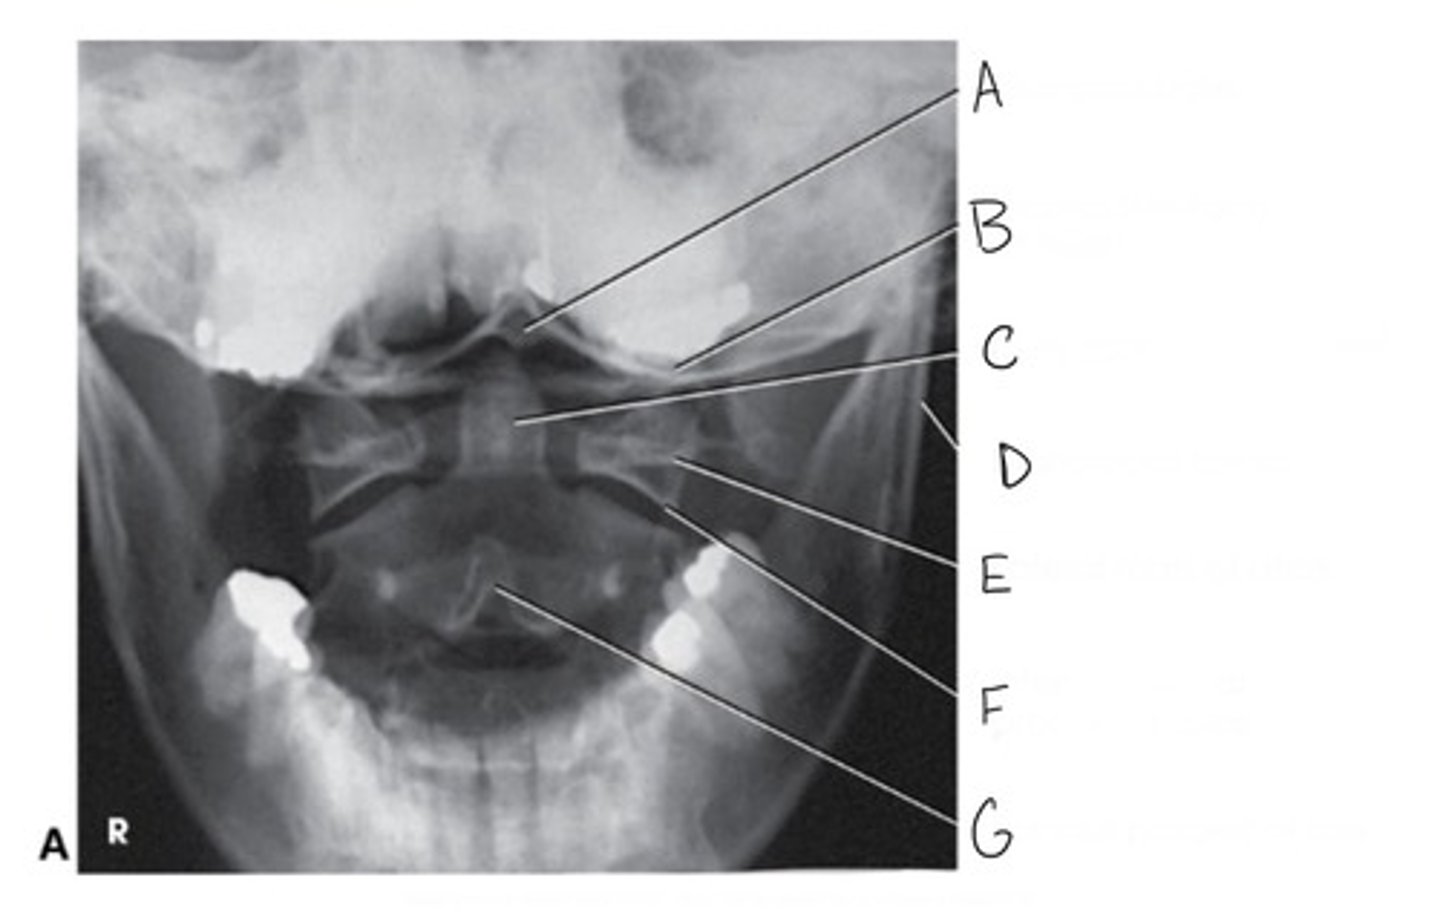

AP (open mouth) of the cervical spine: Atlas & Axis

What projection is this?

Occipital base

What is A?

Occlusal surface of teeth

What is B?

Den (odontoid process)

What is C?

Mandibular ramus

What is D?

Lateral mass of atlas

What is E?

Inferior articular process of atlas

What is F?

Spinous process of axis

What is G?